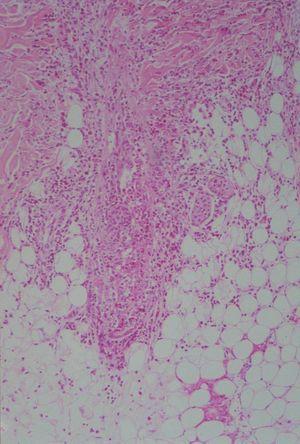

En el estudio histológico podía observarse un moderado infiltrado inflamatorio polimorfo compuesto por polimorfonucleares, eosinófilos y linfocitos, alrededor de los vasos y en el intersticio. Algunos de los folículos se encontraban densamente infiltrados por polimorfonucleares y eosinófilos, que destruían parcialmente la pared, ocupando el infundíbulo y afectando también la glándula sebácea (figs. 2 y 3). Se realizaron tinciones para la detección de estructuras micóticas (PAS y plata-metenamina) que resultaron negativas.

Fig. 3.--Infiltrado inflamatorio eosinofílico de dermis e hipodermis. (Hematoxilina-eosina, x40.)